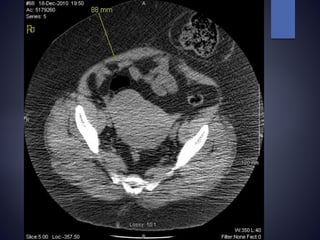

Parastomal hernia

 Abdominal CT scan helpful in c/o difficulty

How are wegoing to get this through that ?

Skin Fascia 9 cm 9cm +2cm = 11cm of Sigmoid Colon 9cm + 6cm = 15cm of Terminal ileum BMI 48.7